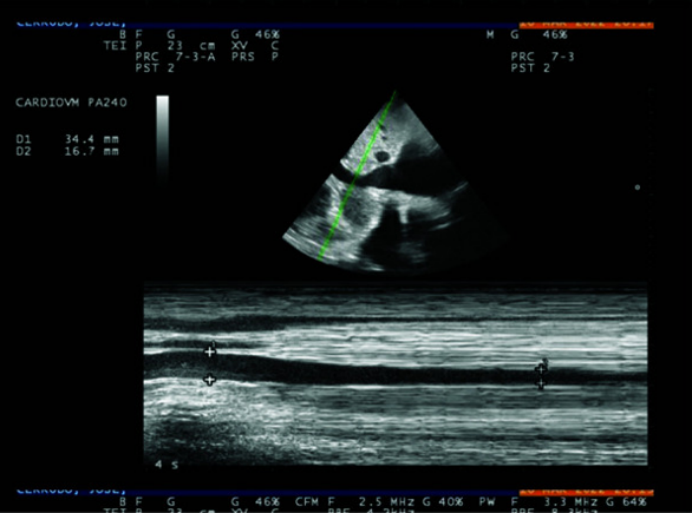

1)短轴缩短率(shortening fraction,SF):SF通过不同维度(直径或面积),反映左室短轴方向的收缩能力。有两种计算方法:①直径法(M超测量):取胸骨旁长轴切面,将M超探头置于乳头肌连接处,确保垂直于室间隔(图13)。计算公式:(舒张末期内径-收缩末期内径)/舒张末期内径。正常范围:24%~36%。②面积法(二维超声测量):取左室短轴切面,探头置于乳头肌连接处并垂直于室间隔,获取舒张末期与收缩末期左室短轴面积(图14)。计算公式:(舒张末期面积-收缩末期面积)/舒张末期面积。正常范围:38%~60%。

图片

13  直径法测量短轴缩短率